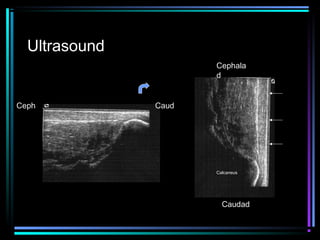

Ultrasound

Cephala

d

Ceph

Caud

Calcaneus

Caudad

Ultrasound – Achilles Tendon

Intrasubstance tear